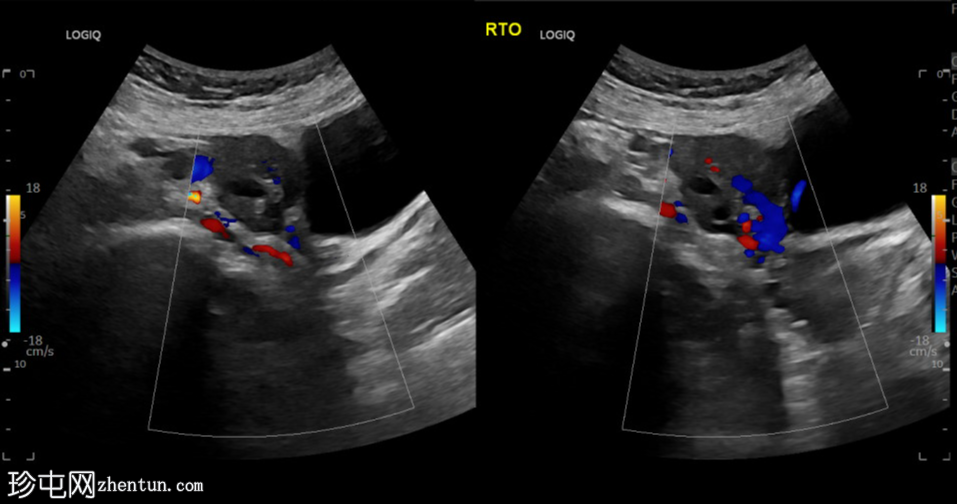

横切面

左侧卵巢明显增大,可见一囊肿,大小约3.2 x 2.3 cm,呈火环征,可能为黄体囊肿。左侧卵巢与子宫之间可见一管状结构,直径约1.3 cm,内含浑浊液体,未见血管,最可能为输卵管积血。以上特征提示可能为左侧异位妊娠。

未见宫内妊娠囊。